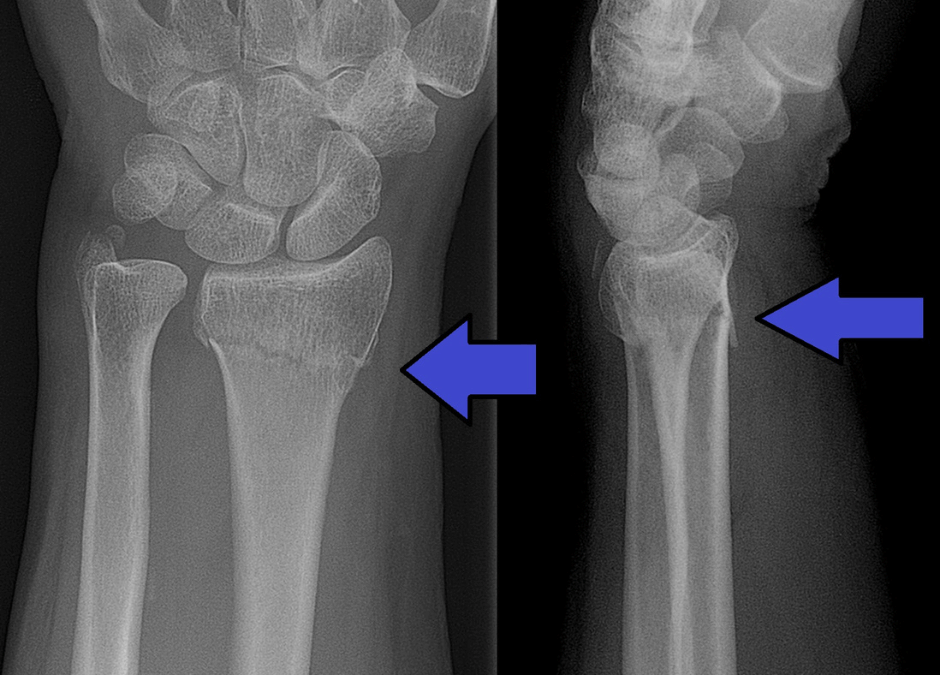

Què és una fractura de Colles i per què es produeix?

La fractura de Colles és una lesió força comuna al braç, especialment entre la gent gran o en situacions on algú cau cap endavant amb la mà estirada. Aquest tipus de fractura afecta la part distal del radi, que és l’os principal de l’avantbraç, i es...

Abraham Colles, va ser un cirurgià irlandès, que el 1814 va descriure per primera vegada aquesta coneguda fractura de canell, molt abans que arribaran els raigs X. Encara que realment es tracta de la part més distal del radi, la més propera al canell, la que es...